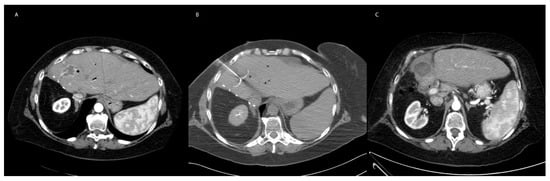

7.2. Cryoablation in Non-HCC Primary Malignancy and Metastatic Disease to the Liver

8.2. Irreversible Electroporation in Non-HCC Primary Liver Malignancy and Metastatic Disease to the Liver